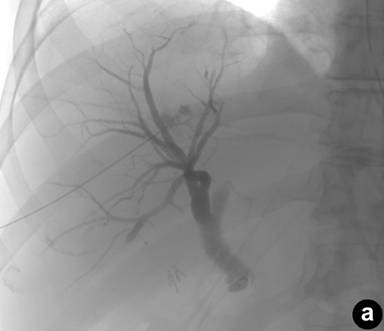

The patient is a 68-year-old man who presented with jaundice, weight loss, abdominal pain, and early satiety. He had a recent history of gallstone pancreatitis, post ERCP with sphincterotomy and common bile duct stent placement and cholecystectomy. He had been discharged home in good condition, but returned due to a severe gastric outlet obstruction. He underwent repeat ERCP, but the procedure was aborted secondary to a duodenal stenosis. His biliary system was then drained with a percutaneous biliary drainage with a 8-Fr internal-external biliary drain (Flexima®, Boston Scientific, Natick, MA, USA). Figure 1a demonstrates a lack of contrast filling the duodenum by percutaneous transhepatic cholangiography (PTC), and Figure 1b demonstrates the placement of the drain. An endosonography was then performed which confirmed a mass in the head of the pancreas. This was found by fine needle aspiration to be pancreatic adenocarcinoma with tumor invading into the duodenum. A staging helical abdominal CT with pancreatic protocol was performed, and one week later the patient underwent a classic pancreaticoduodenectomy with distal gastrectomy. At the end of surgery the percutaneous biliary drain was removed. The patient tolerated the procedure well. On post-operative day number three, the patient became acutely hypotensive and had a melanotic stool with a drop in hemoglobin from 9.0 g/dL pre-operatively to 6.4 g/dL (reference range: 12.0-16.0 g/dL) requiring transfusion of 3 units of packed red blood cells. Endoscopy on two consecutive days identified the gastric anastomosis but found only clotted blood in the stomach with no source of bleeding. The patient’s hematocrit later stabilized, and he was discharged home on postoperative day seven.

Figure 1. a. Percutaneous transhepatic cholangiography with filling defect of the duodenum. b. Percutaneous biliary drainage placement and filling of the duodenum. |